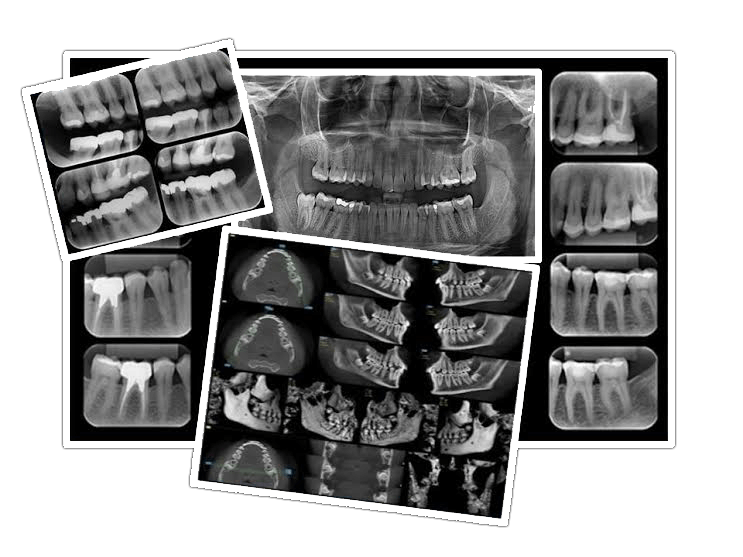

Ident-Rad

Ident-Rad é a mais nova solução online de prontuários odontológicos. Cadastrando-se você pode acessar seu prontuário de qualquer lugar!

É paciente? Converse com seu dentista, peça já o seu cadastro!

É dentista? Venha conhecer nosso sistema, faça já seu cadastro!